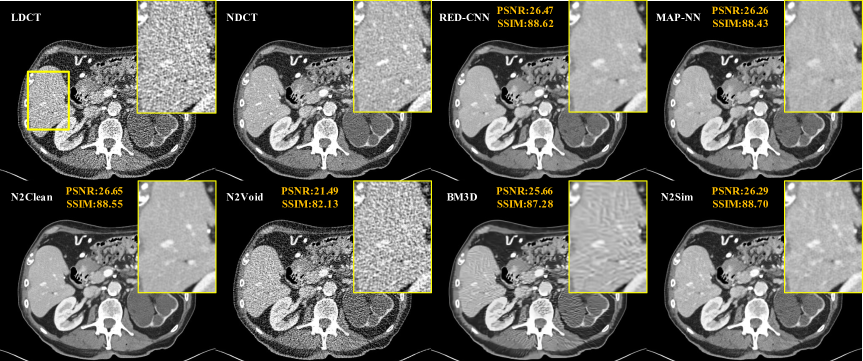

We first evaluated Noise2Sim on the commonly used Mayo clinical dataset containing LDCT and NDCT image pairs, demonstrating that Noise2Sim without using any annotation is comparable to and sometimes even better than supervised learning methods. Popular supervised deep LDCT denoising methods RED-CNN  (?) and MAP-NN  (?) were selected for comparison. Noise2Clean that is the plain supervised version of Noise2Sim serves as the baseline. Also, we selected BM3D  (?) and Nosie2Void  (?) for comparison, which are the most popular traditional denoising method and the representative unsupervised deep denoising method respectively. Note that BM3D has the best performance among the traditional denoising methods as demonstrated in  (?) for LDCT denoising. Both visual results and quantitative Structural Similarity Index (SSIM) and Peak signal-to-noise ratio (PSNR) results were used to evaluate the denoising performance.

Figure 1: Superior/comparative Noise2Sim results on the Mayo LDCT dataset. The yellow ROIs indicate that detail structures are better preserved using Noise2Sim than other methods in reference to the normal-dose CT image. The display window is [-160, 240] in Hounsfield unit (HU), along with PSNR and SSIM values.

The visual results in Fig. 1 also illustrate that Noise2Sim is better than the supervised methods in preserving structural details, as indicated by the zoomed ROIs in the yellow bounding boxes, in reference to the normal-dose CT image. Clearly, the supervised methods tend to remove noises aggressively while Noise2Sim tries to preserve informative details. Our results show that Noise2Void does not work for structured CT noises, and the BM3D results are either over-smoothed or compromised with structured artifacts. In contrast, Noise2Sim has significantly better performance in reducing structured noises and preserving content structures.